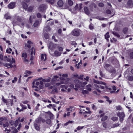

We implemented our algorithm using the Python Optimal Transport (POT) library 222https://github.com/rflamary/POT which include GPU-accelerated versions of Sinkhorn regularization. We used Nvidia GeForce RTX 2080 Ti for our experiments. Pytorch framework was used for StainGAN 333https://github.com/xtarx/StainGAN and CNN3 444https://github.com/neerajkumarvaid/Nuclei_Segmentation implementations. We evaluated our approach against Reinhard et al. [12], Macenko et al.[7], Khan et al. [4], Vahadne et al. [17], and StainGAN [14].

| Source | Reinhard[12] | Macenko[7] | Khan[4] | Vahadane[17] | StainGAN[14] | (Ours) | (Ours) | Target |

|---|---|---|---|---|---|---|---|---|

4.1 Stain Normalization Evaluation

We used MITOS-ATYPIA’14 challenge dataset for evaluating our stain normalization. The dataset includes same tissue sections scanned by two different scanners (Aperio-A and Hamamatsu-H) with total 424 X20 A-H frame pairs, 300 training and 124 testing. Images from scanner A are normalized and matched against the real corresponding images from H (ground truth). As in StainGAN [14], 10,000 random (256256) patches from 300 training frames were used for training (26 epochs with the regularization parameter , learning rate 0.0002, Adam optimizer with a batch size of 4) and 500 patches from 124 testing data used for evaluation. The visual and quantitative comparisons are shown in Figure 3 and Table 1, respectively. For the traditional case (one reference and source), our results are very similar to Reinhard et al. [12] since they also do color matching in Lab space, but our results improve drastically given two reference images. The references in our case span patches with different amounts of background visible. We also tested with different reference images and we show that we get a tighter bound as long as the references contain different amounts of background visibility; see Figure 4 for the box plots of SSIM for different references.